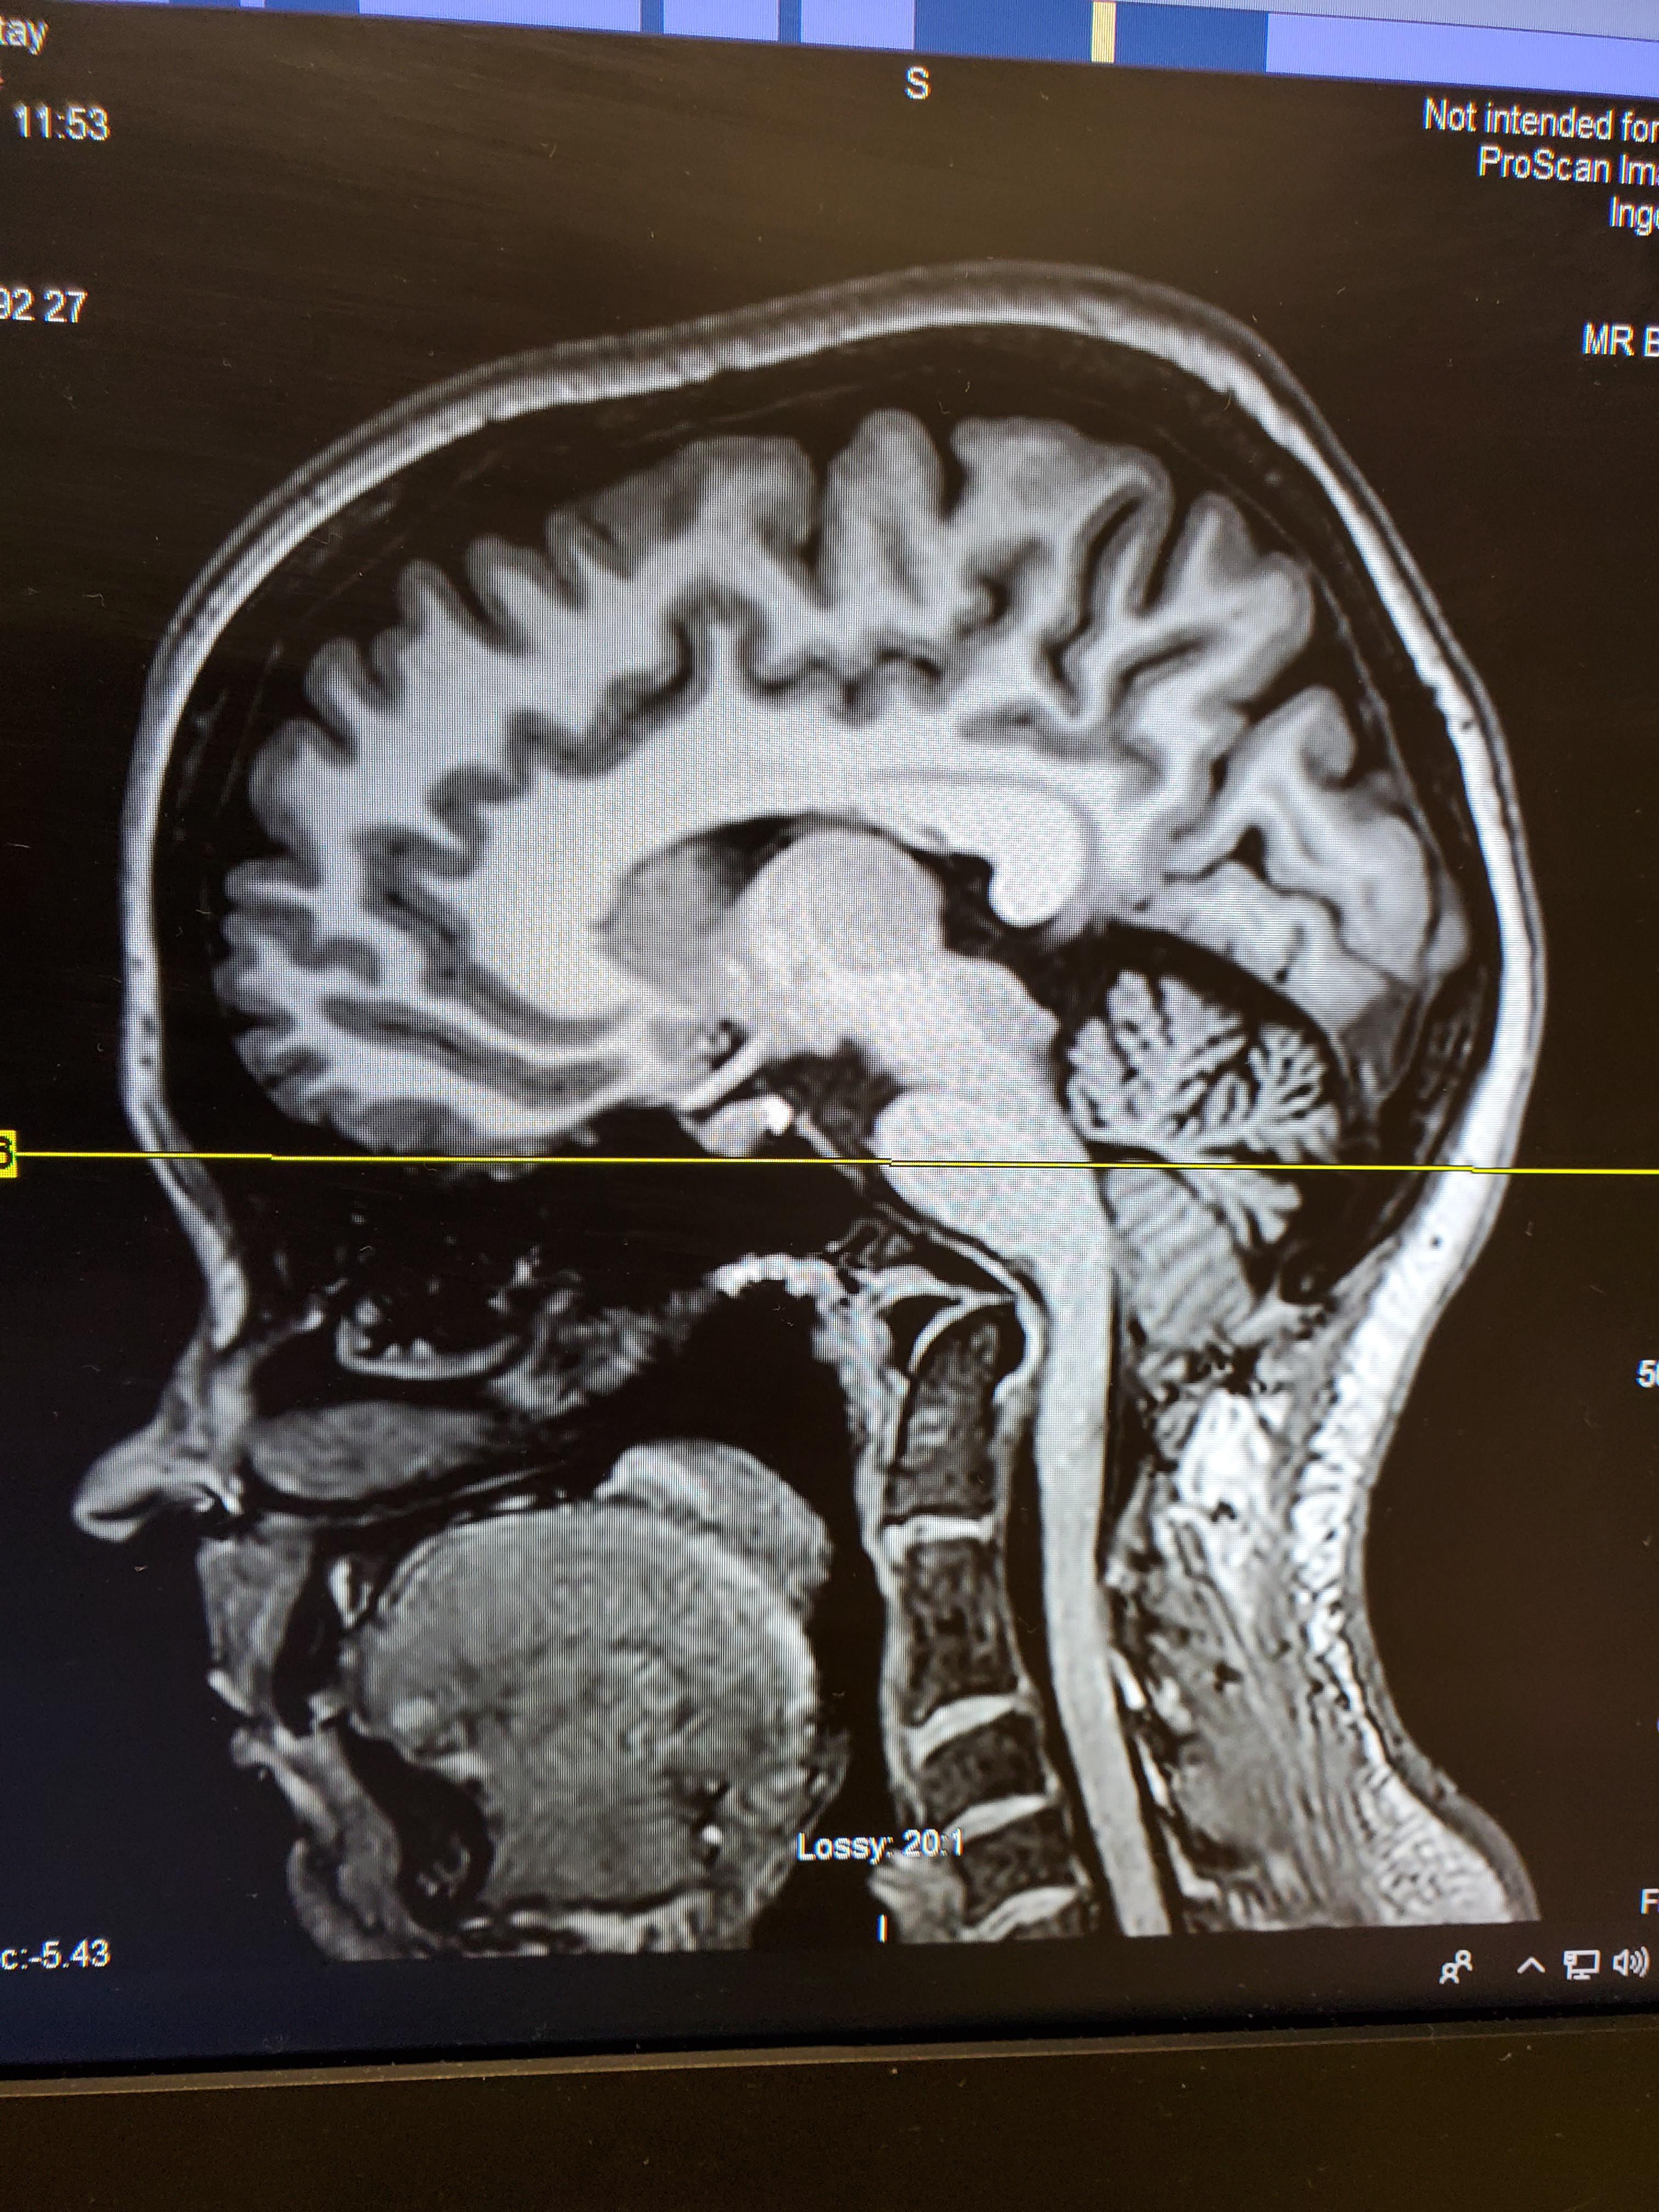

Does this look like Chiari Malformation? Chiari Malformation Forums What Does Chiari Neck Pain Feel Like Learn about the common symptoms of chiari malformation, a condition where the cerebellar tonsils extend into the spinal canal. These headaches are felt near the. Chiari malformation is a condition in which brain tissue extends into the spinal canal. It can cause headaches, neck pain, balance. The most common symptom associated with a chiari malformation is occipital headaches. Chiari malformation. What Does Chiari Neck Pain Feel Like.

MRI features of the dog in case No. 1. Chiarilike malformation (CM What Does Chiari Neck Pain Feel Like Headache, neck pain, dizziness, balance problems,. Chiari malformation type i is a congenital or acquired problem in which the cerebellum bulges through the skull and puts pressure on the brain and spinal cord. These headaches are felt near the. It can cause headaches, neck pain, balance. Learn about the common symptoms of chiari malformation, a condition where the cerebellar tonsils. What Does Chiari Neck Pain Feel Like.